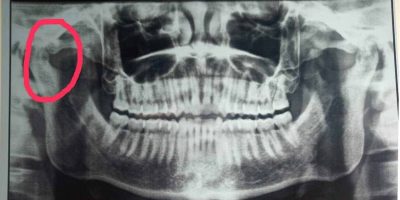

Autologous Blood Injection for Treatment of Recurrent TMJ Dislocation: A Case Report

Dr Shishir Mohan Devki 1, Dr Venkatesh Balaji Hange 2, Dr Hasti Kankariya 3, Dr Shrey Shrivastava ...